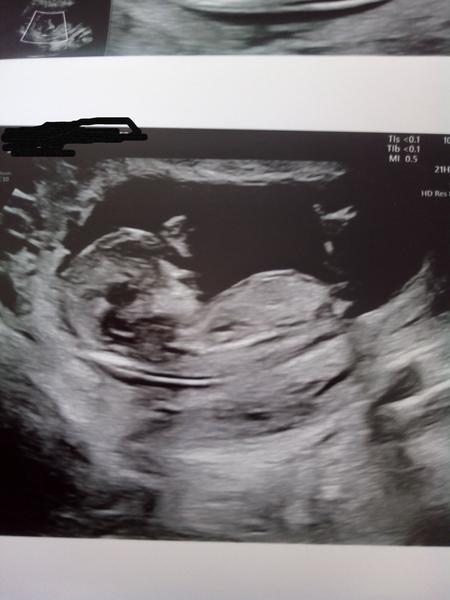

@juliemichal Tak byla to minule noha a ne pahorek 😁😄 tak gratuluji 😇

@lilian2111 moc děkuji 😘 😍 vůbec tomu nemůžu věřit 😀 😀 ty jo o Matea jsme se snažili 4 roky,říkám si to bude určitě holčička 😀 a nic 😀 u Tobíka jsme se snažili 2 roky,říkám si,tak to bude holčička a ono nic 😀 teď jsme se vůbec nesnažili,mimi mělo být až za 6 let a ejhle otěhotněla jsem neplánovaně a konečně jsem se dočkala holky 😘

@juliemichal ja jsem taky otěhotněla přes antikoncepci, neplánovaně. A taky holka po 3 klucich. A nejhorší těhotenství. Pořád jsme obě o neco bojovaly. A je tu s námi a je dokonalym posledním dilkem do našeho puzzle.

@sebinka123 jé to je krásné zlatíčko 😍 taky jsme neměly lehký průběh 😀 hospitalizace skrz mimoděložní atd atd 😀 😀 no já antinu nebrala,používali jsme přerušovanou metodu 😀 a ejhle je tam malá Anita Marie 😍